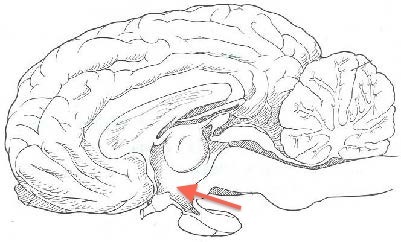

Which part of the brain is indicated by the arrow?

Hypothalamus